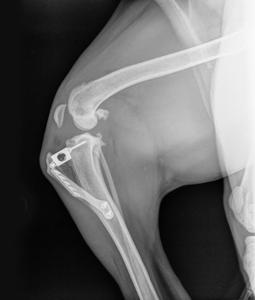

진단 방법

- 임상 증상과 이학적 검사(무릎의 불안정성 확인)

- 방사선(X-ray) 촬영

- 관절 초음파 검사 등 영상 진단